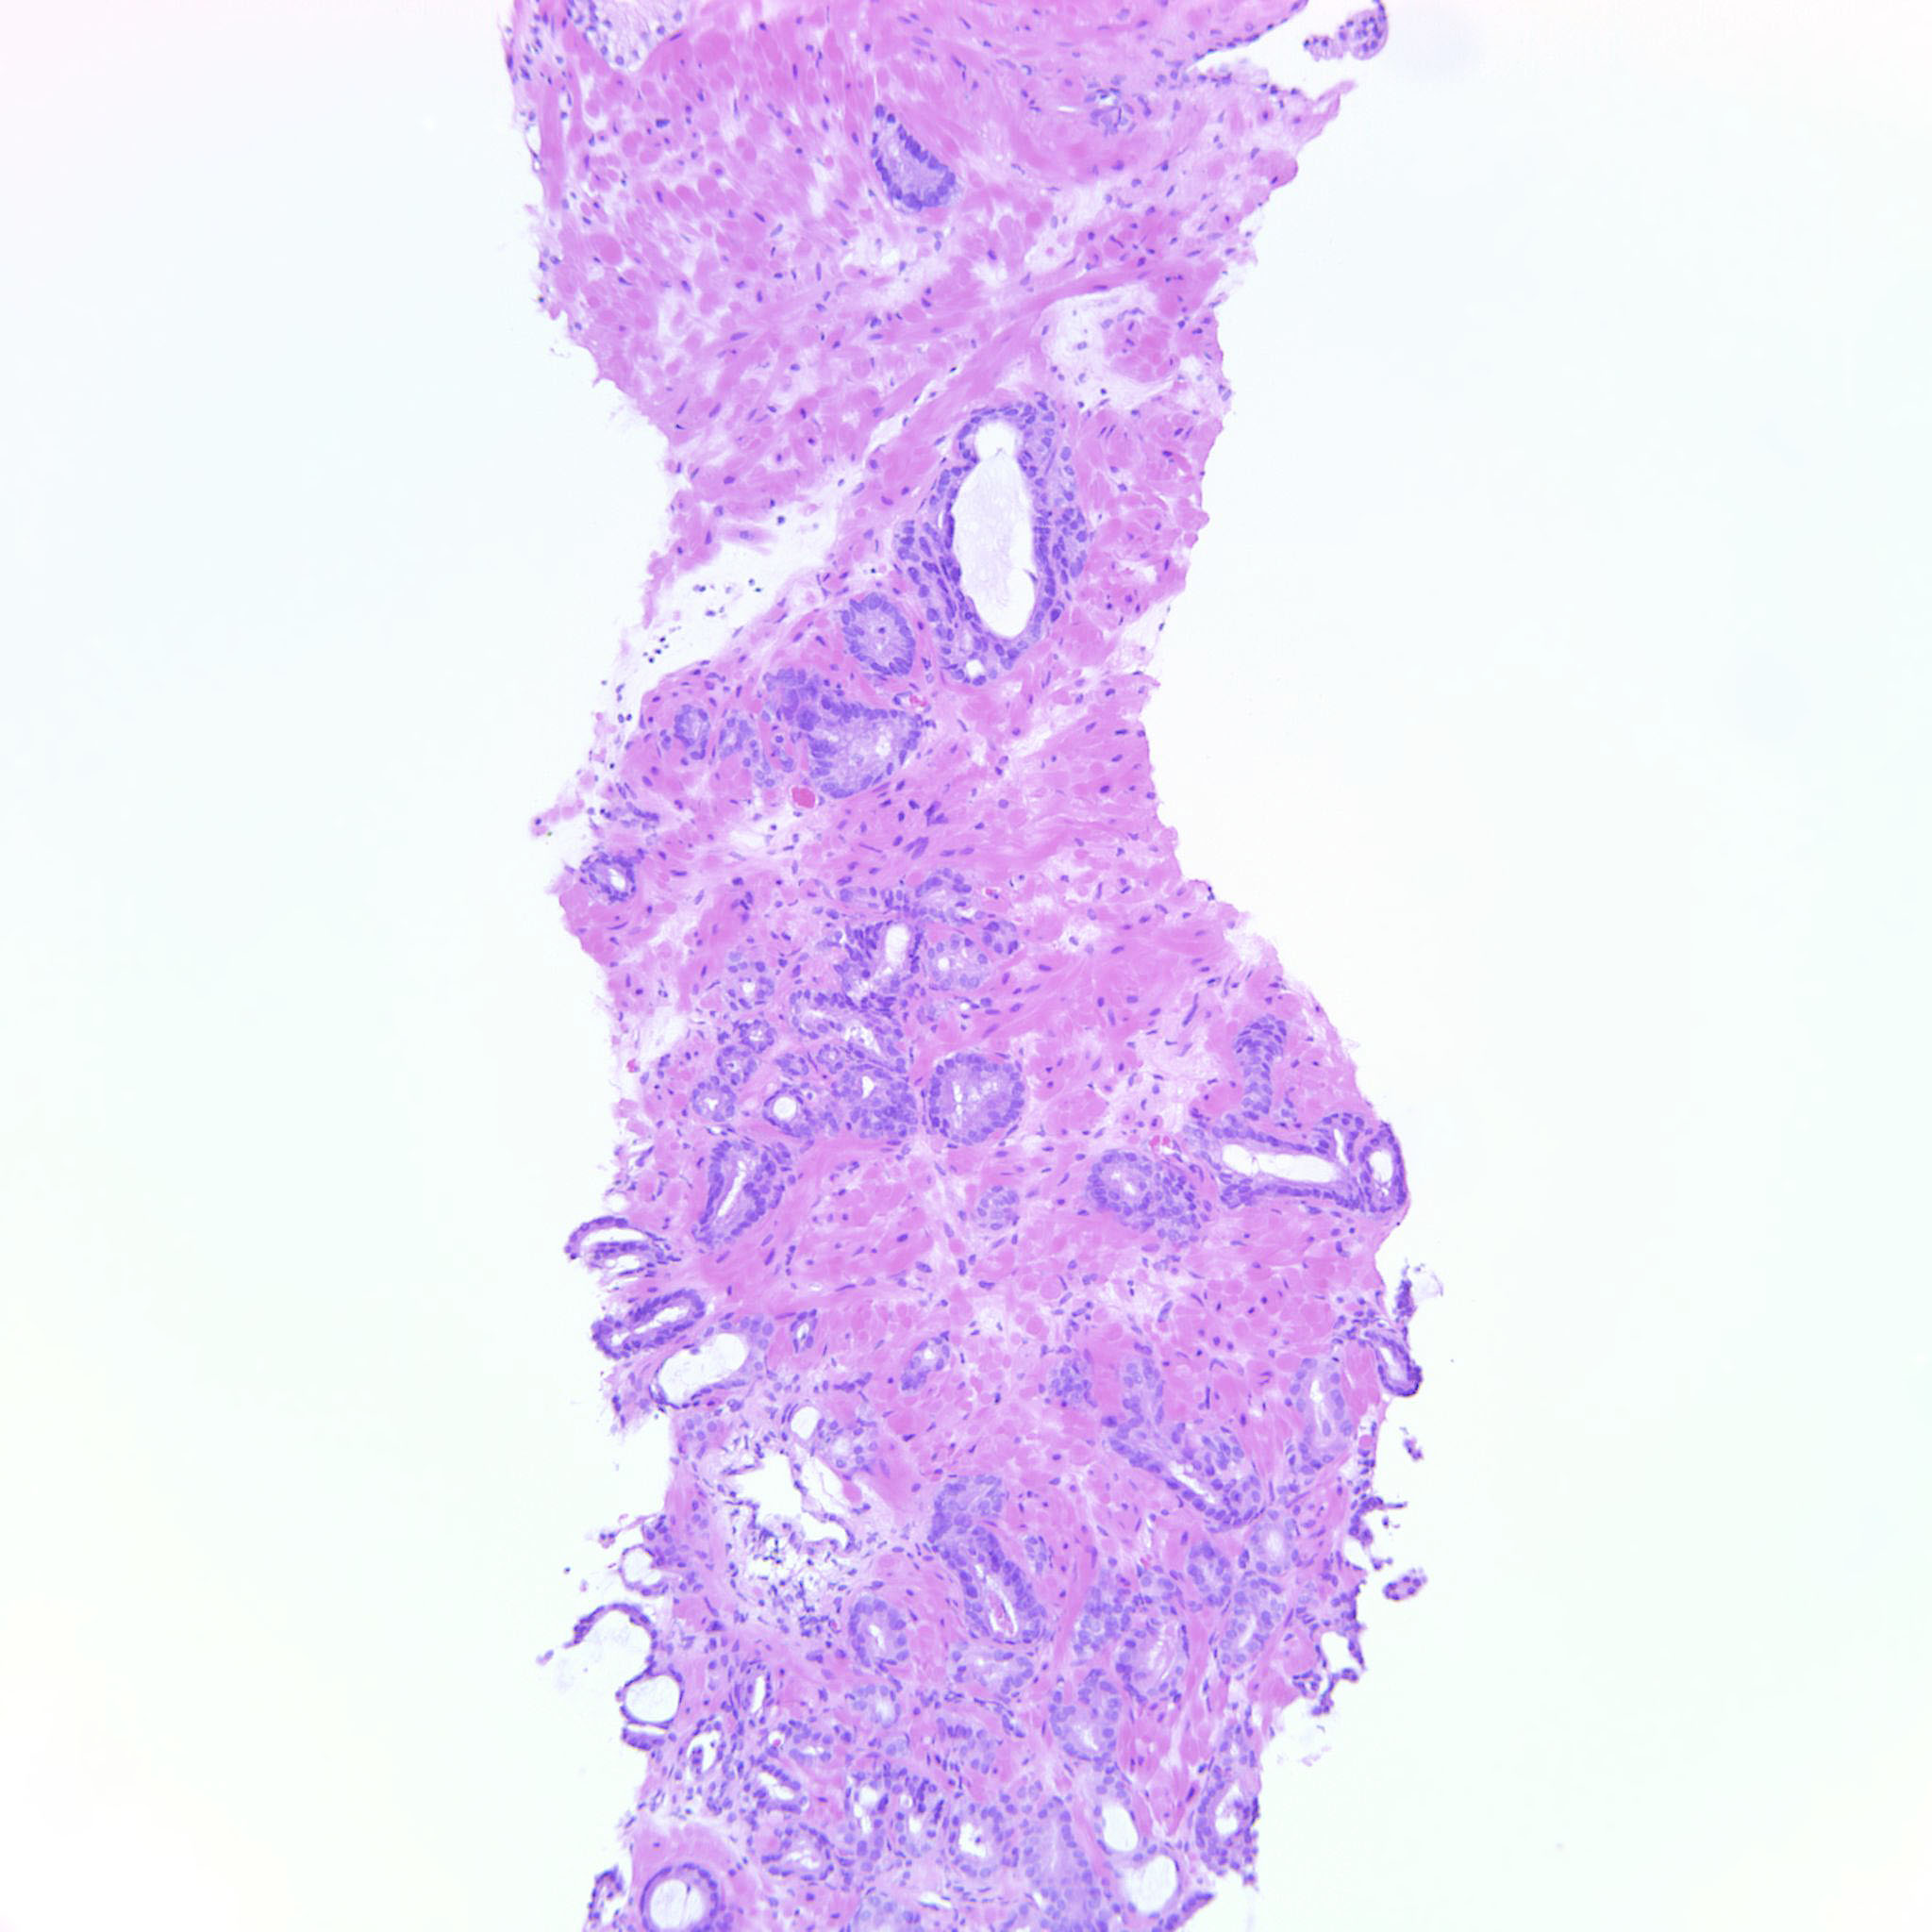

Consensus grade: GS 3+3=6 (ISUP 1)

Case description (by case creator):

3+3=6 bordering towards 3+4. There are rare seemingly poorly formed glands but they can still be overlooked.